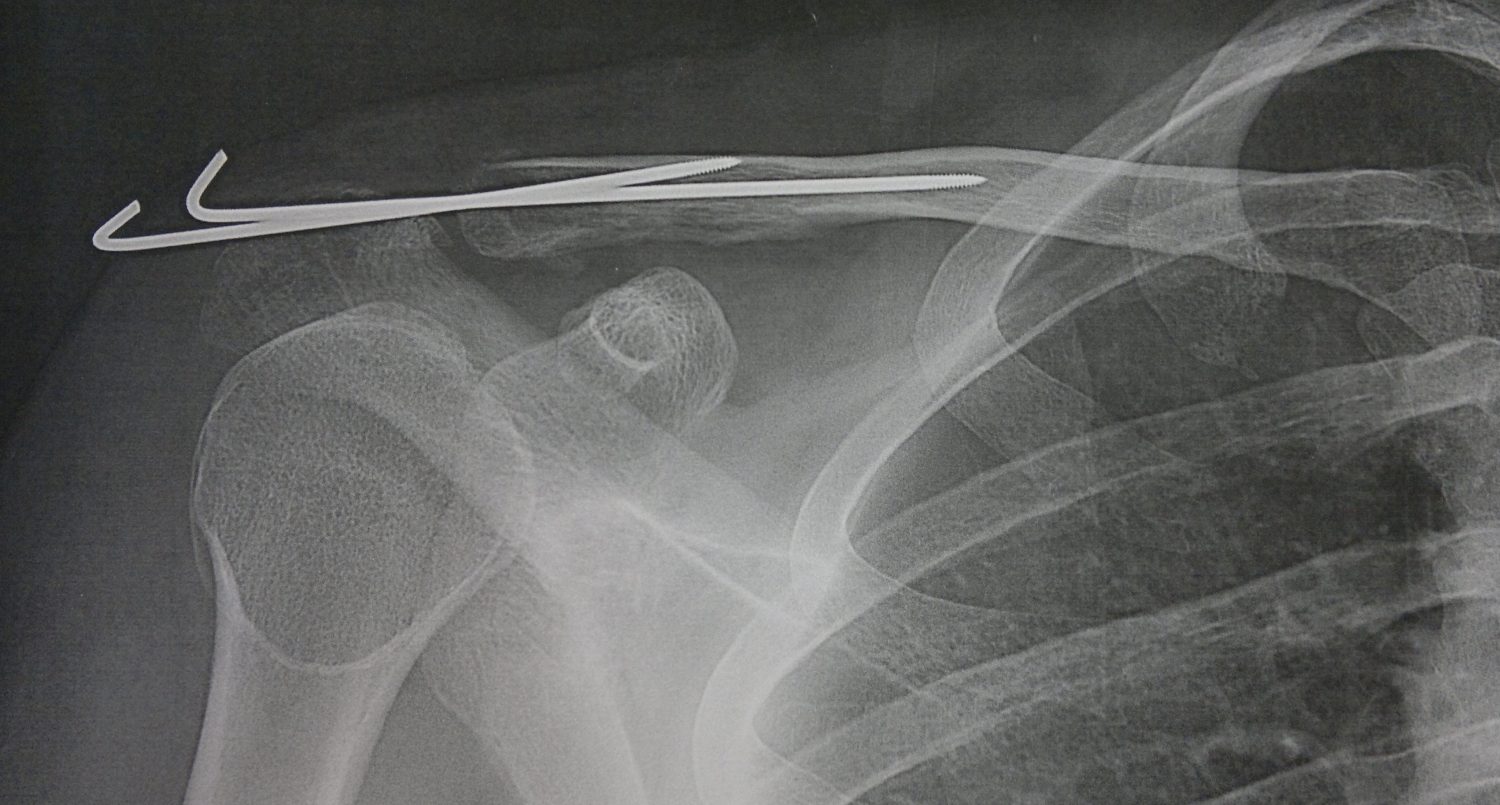

From www.dr-touchard.fr

fracture epaule post op profil Docteur Touchard Fracture Epaule Et Sport Quels examens médicaux pour savoir si son épaule est cassée ? En combien de temps l'os se consolide ? Le temps de guérison d’une fracture de l’épaule dépend de la gravité de la lésion et du type de traitement. Un orthopédiste explique s’il est bon de refaire du sport après une pause forcée due à une fracture et comment s’y. Fracture Epaule Et Sport.

fracture epaule post op face Docteur Touchard Fracture Epaule Et Sport Un orthopédiste explique s’il est bon de refaire du sport après une pause forcée due à une fracture et comment s’y prendre. Quels sont les symptômes d'une fracture de l'épaule? Quels examens médicaux pour savoir si son épaule est cassée ? Quand elle n’est pas opérée, comment immobiliser l’épaule ? Quelles sont les techniques chirurgicales ? La fracture de l’omoplate. Fracture Epaule Et Sport.